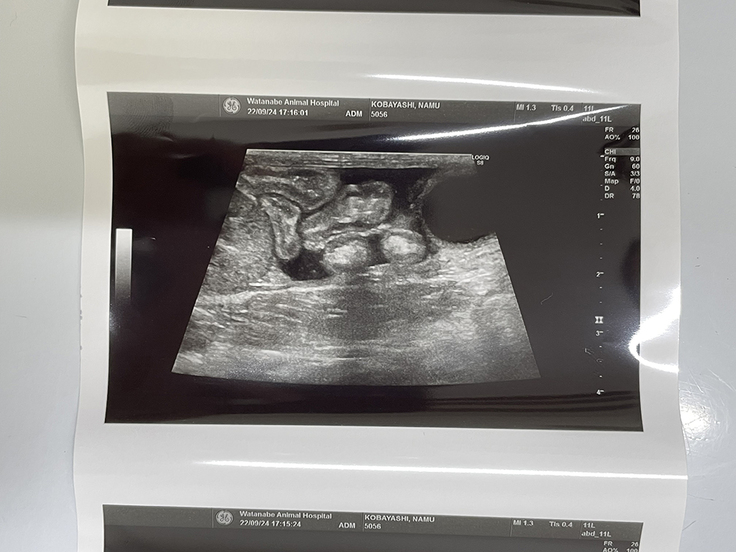

9月24日現在↑ 事故の影響で腹腔内に溜まっている腹水(黒い部分)のエコー

排尿の回数は少し多いが、排便は順調。